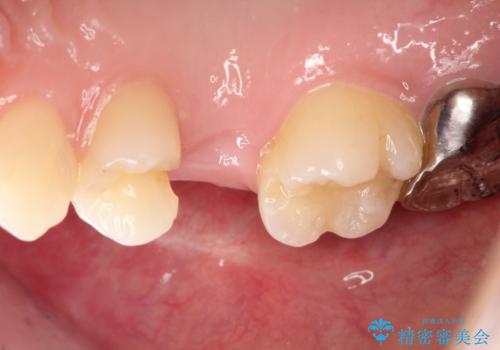

インプラント埋入手術は1回で全て行い、2ヶ月後にはセラミック治療で、審美回復と機能回復をしました。

来院回数が少なく、しっかり食事もできるとの事で非常に喜んで頂けました。